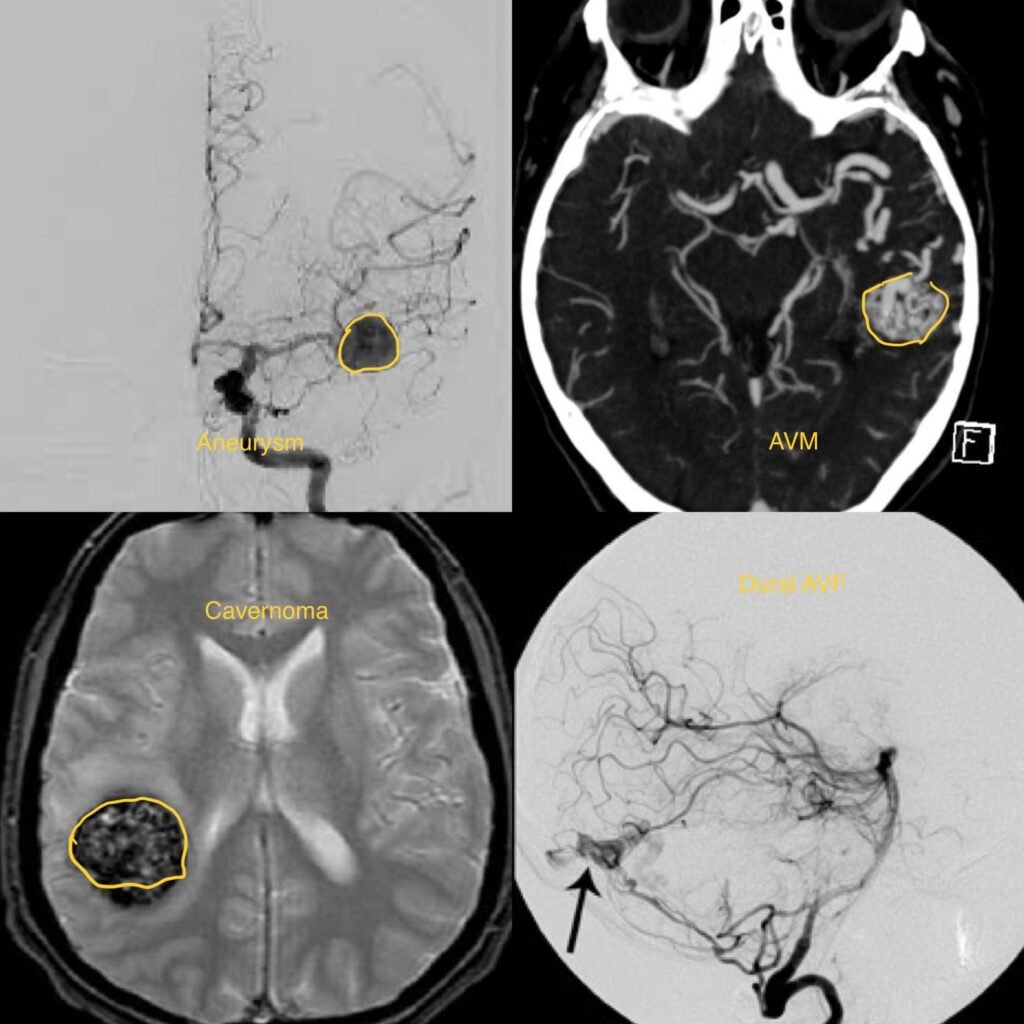

Cerebrovascular diseases are a group of conditions that affect the blood vessels supplying the brain. These conditions can disrupt blood flow to the brain, leading to various neurological symptoms and potentially life-threatening complications. Common cerebrovascular diseases include stroke, transient ischemic attack (TIA), and cerebral aneurysms.

- Diagnosis typically involves a thorough neurological examination, medical history, imaging studies such as CT scans, MRI, or angiography, and sometimes blood tests to evaluate the extent and cause of the cerebrovascular disease.

- Treatment options vary depending on the specific condition but may include medication (such as blood thinners or clot-busting drugs), lifestyle modifications (such as smoking cessation, exercise, and diet changes), minimally invasive procedures (such as angioplasty or stenting), or surgery (such as clot removal or aneurysm clipping).